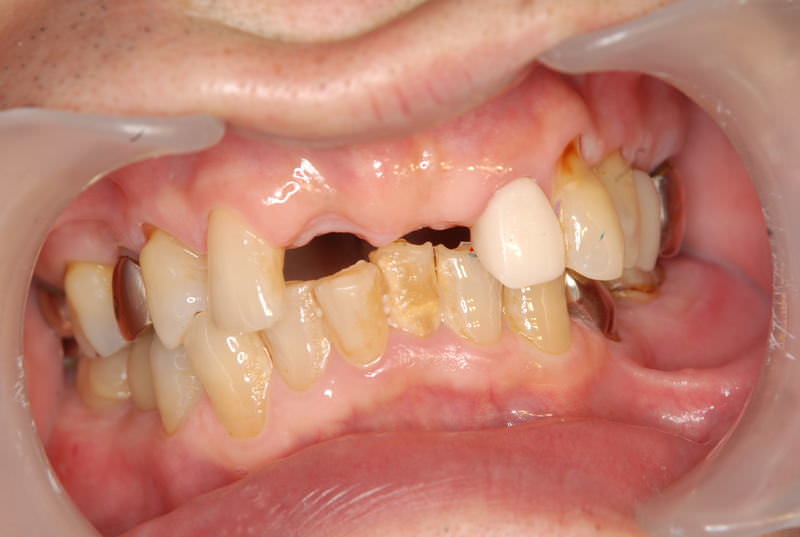

症例140代 男性 主訴 奥歯に歯を入れたい、しっかり噛みたい

治療前

治療後(5年経過)

主訴 奥歯がない為、食事が不自由である。入れ歯は煩わしいので、固定制のインプラントにして欲しいと訴え来院。口腔内全体で6本のインプラントを埋入。仮歯にて神経筋機構、顎関節のバランスを整え、リハビリを経て、約5ヶ月後にジルコニアを装着。

リスクとしては、外科的侵襲がある。デメリットは、保険外診療の為、経済的負担がある。

費用 316万(税込) (オペ・仮歯・最終補綴物まで含む)